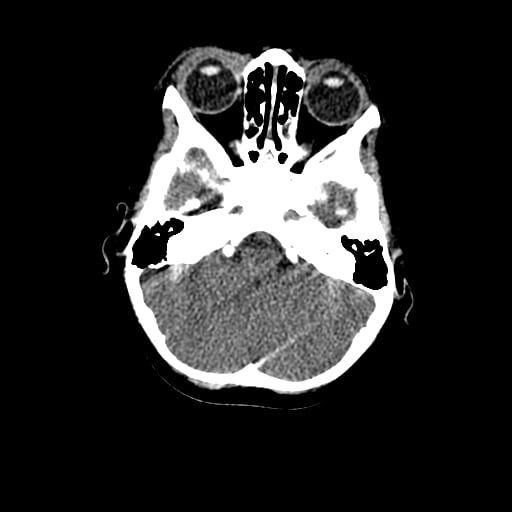

Age: 1

Sex: Male

Indication: Fall